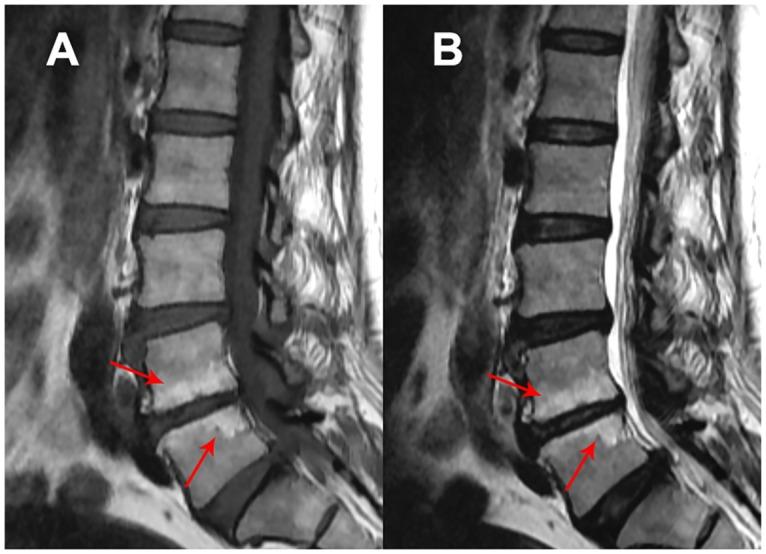

A descriptive cross sectional study was carried out on 106 patients with chronic mechanical low back pain. T1, T2 sagittal lumbar MRI scans were used to assess the severity of LDD and Modic changes. 62 SNVs in ten candidate genes (ACAN, IL1A, IL1B, IL6, MMP3, ADAMTS4, ADAMTS5, TIMP1, TIMP2 and TIMP3) were genotyped on Sequenom MassARRAY iPLEX platform. Multiple linear regression analysis was carried out using PLINK 1.9 in accordance with additive genetic model. In-silico functional analysis was carried out using Provean, SIFT, PolyPhen and Mutation Taster.

对106例慢性机械性下腰痛患者进行了描述性横断面研究。使用T1、T2矢状位腰椎MRI扫描评估LDD和Modic改变的严重程度。在Sequenom MassARRAY iPLEX平台上对10个候选基因(ACAN、IL1A、IL1B、IL6、MMP3、ADAMTS4、ADAMTS5、TIMP1、TIMP2和TIMP3)中的62个SNV进行基因分型。使用PLINK 1.9根据加性遗传模型进行多元线性回归分析。使用Provean、SIFT、PolyPhen和Mutation Taster进行计算机功能分析。